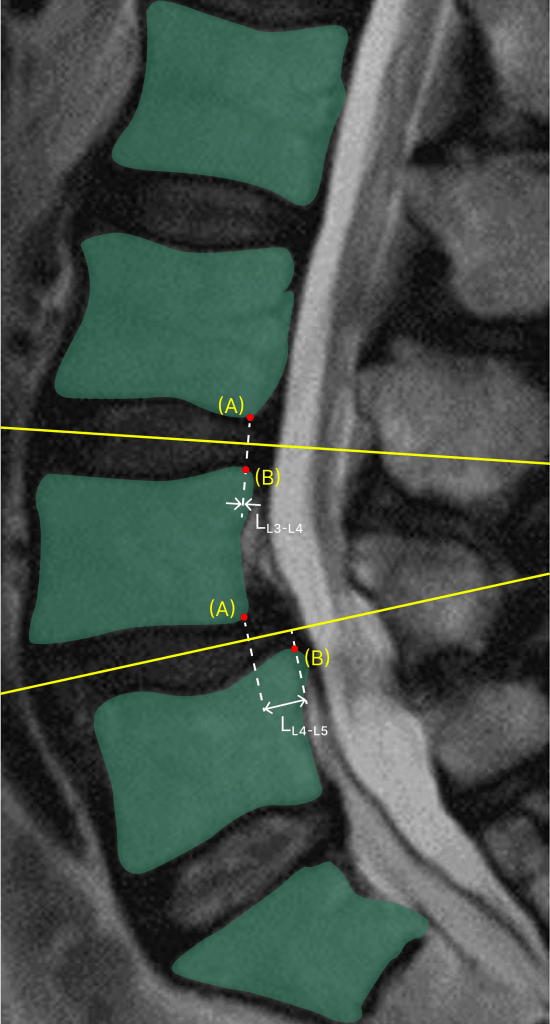

Designing and implementing three new sets of DICOM series (Summary, Sagittal, Axial) enhanced by AI to be viewed alongside original images, optimizing visual appeal and user experience through collaboration with physician consultants and detailed design systems, ultimately bridging the gap between machine learning outputs, customer requirements, and business goals.

I began by delving into various visual possibilities and experimenting with them alongside our physician consultants. Gathering feedback from these sessions, I collaborated with the team to refine and solidify the designs.

Throughout this process, I used my clinical expertise from supporting 1000s of cases and learning physician workflows. For instance, when presenting to the engineering team, I emphasized the technical aspects of the product’s implementation, using detailed schematics and mock-ups to illustrate feasibility and functionality.